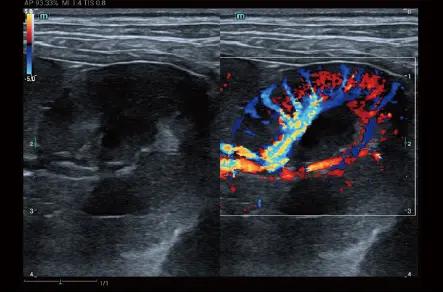

HR Flow

Иновативна технология подобряваща визуализацията на микросъдови и сложни модели на потока, въз основа на новаторския алгоритъм на Mindray Animal за обработка на сигнала.

HR Flow

Innovative technology, based on Mindray Animal's Advanced processing algorithm, which effectively improving the dynamics of blood flow and providing high performance on both penetration and resolution.